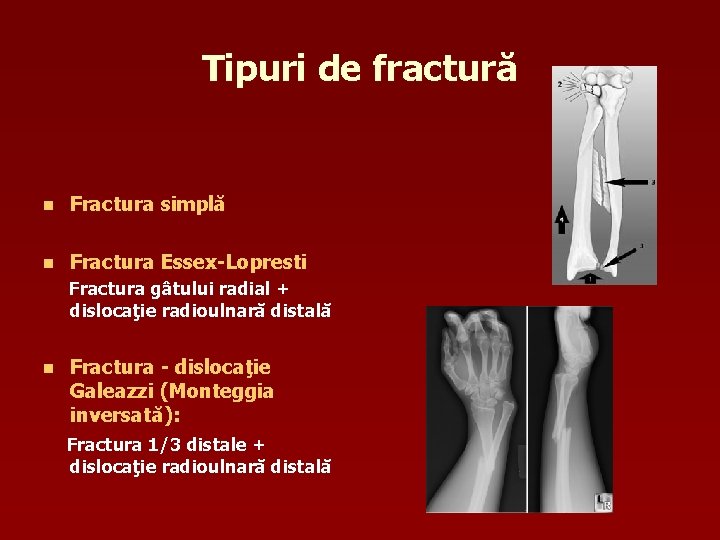

Tipuri de fractură n Fractura simplă n Fractura Essex-Lopresti Fractura gâtului radial + dislocaţie radioulnară distală n Fractura - dislocaţie Galeazzi (Monteggia inversată): Fractura 1/3 distale + dislocaţie radioulnară distală